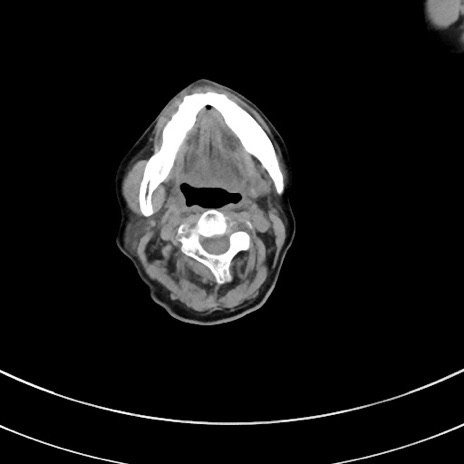

冠状断像

症例33(横断像)

【症例】70歳代 女性

【現病歴】延髄病変の精査・加療にて神経内科入院中。本日より心窩部痛あり。